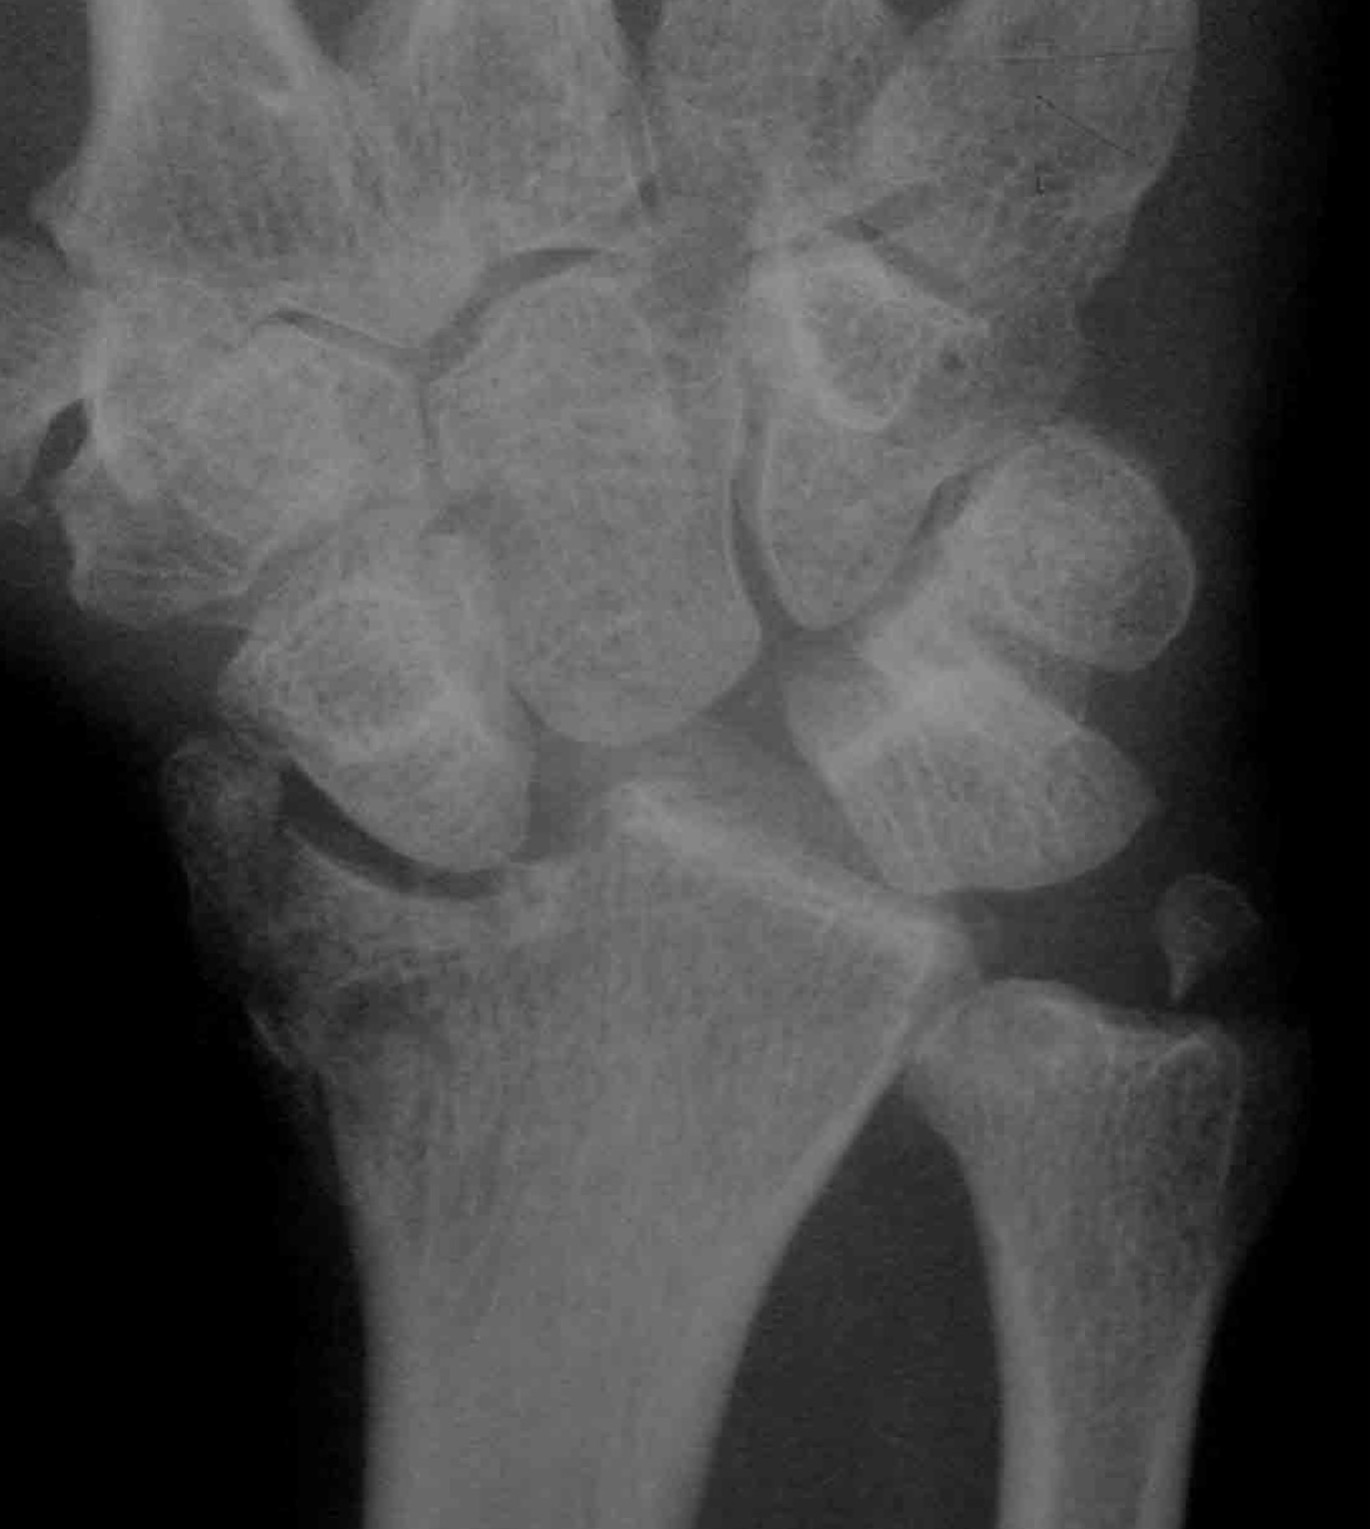

AP X-ray

Disruption of Gilula's 3 smooth carpal arcs / triangular lunate

Normal versus disruputed Gilula's carpal arcs

Piece of pie / triangular appearance of lunate

1. Perilunate dislocation

Lunate remains aligned with distal radius

Capitate dislocates dorsally

2. Lunate dislocation

Lunate dislocates / usually volar

Carpus remain aligned with distal radius